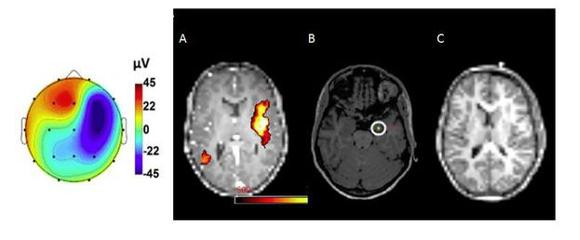

Das Forschungsteam um den Physiker Dr. Claus Kiefer und die Mediziner Eugenio Abela, Kaspar Schindler und Roland Wiest aus dem Support Center for Advanced Neuroimaging (SCAN) am Institut für Diagnostische und Interventionelle Neuroradiologie und der Universitätsklinik für Neurologie am Inselspital nutzte die neue Methode in einer Pilotstudie mit acht Epilepsie-Patienten. Dabei fand man heraus, dass die neu entwickelte MR Sequenz Magnetfeldstörungen selbst in tiefen Regionen des Hirns sichtbar macht, welche ein sonst zum Einsatz kommendes Oberflächen-EEG nie erreicht. Damit wird es möglich, den Ursprung der epileptischen Anfälle noch genauer einzugrenzen, was v.a. denjenigen Patienten zu Gute kommt, welche im „normalen“ MRI keine strukturellen Auffälligkeiten zeigen.

Zusätzlich zeigten die Forscher auf, dass nach einer Operation anfallsfreie Epilepsie-Patienten auch tatsächlich keine derartigen Magnetfeldstörungen mehr aufweisen – ihr Hirn also ähnlich „störungsfrei“ funktioniert wie das gesunder Menschen. Patienten, welche weiterhin Anfälle hatten, zeigten dagegen noch die typischen pathologischen Signale.